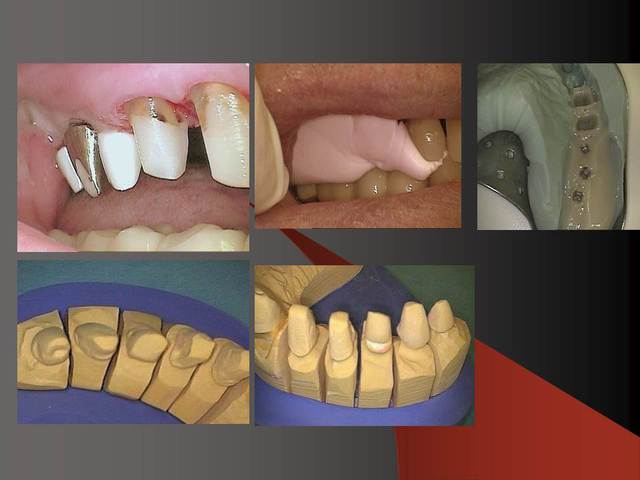

Le dernier photo cela montre le système des Prep Caps :

il y a deux point de réferences en rouge c´est où finit la prep caps et en jaune où commence la prep caps (à la base) .

Je place des couronnes, des bridges et des pilliers implantaires en zircone.

C'est donc des blocs usinés et ensuite frittés (cuit).

Pour la paroie osseuse en vestibulaire de l'implant, le fait qu'il y ai ou pas un gummy smile me change pas grand chose, l'os est selon moi trop mince pour être stable dans le temps.

Pour la zircone les laboratoires ont le choix entre des rounds isostatiques ou axial pressés, pour moi même je préfère le isostatique car il y a beaucoup moins de shipping :-)